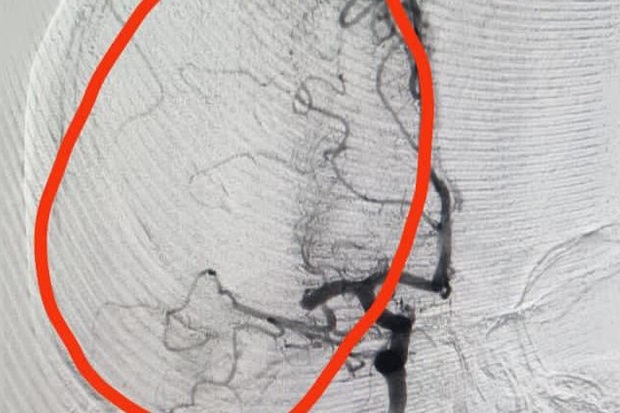

В регкомитете здравоохранения рассказали, что 43-летняя жительница Санкт-Петербурга находилась в гостях у родственников в Волгограде, те испугались и вызвали скорую помощь. Пациентку привезли в больницу, после КТ-ангиографии головного мозга и КТ волгоградские медики обнаружили у нее тромбоз средней мозговой артерии справа.

Тогда хирурги провели женщине тромбэкстракцию с регрессом неврологической симптоматики. Медицинское оборудование, позволяющее такое вмешательство, было ранее приобретено в рамках федерального проекта под названием «Борьба с сердечно-сосудистыми заболеваниями» национального проекта «Здравоохранение».